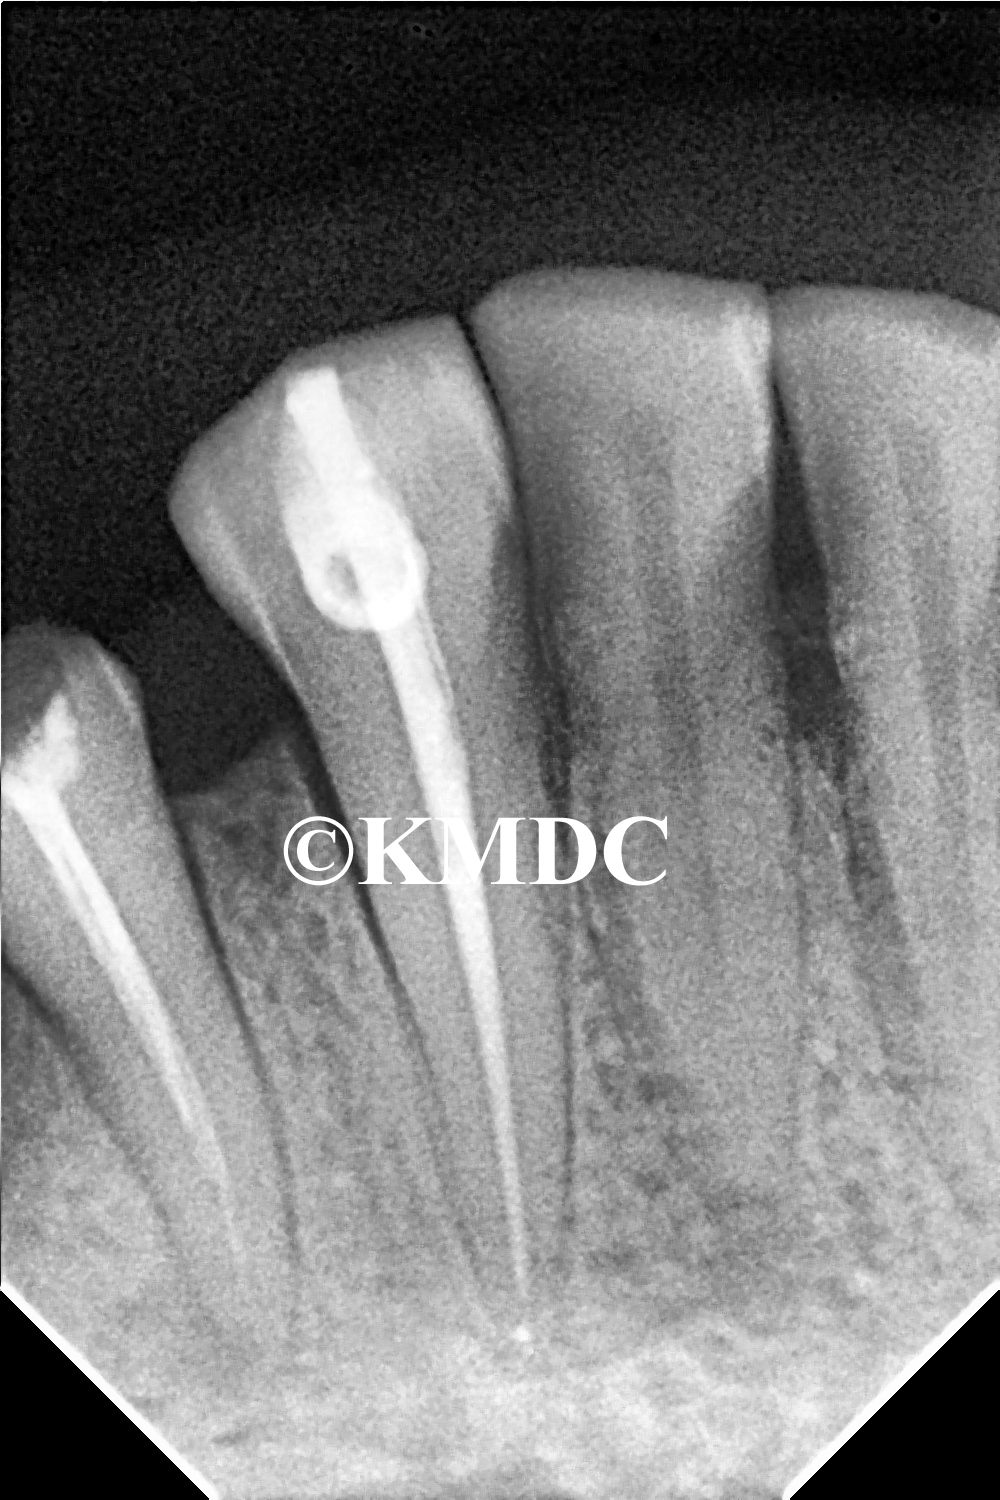

Clinical Gallery